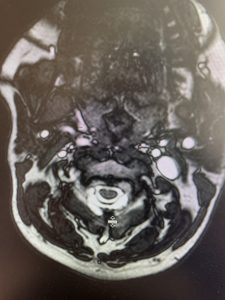

(1b) Hyperintense signal (arrow) at the C3-4 interspinous space consistent with ruptured interspinous ligament,C4-5 (Fig. 1a and 1b).

The fluid was possibly consistent with CSF versus chronic hematoma. The patient was also noted to have a high signal within the interspinous space of C3-C4. This high signal was consistent with a ruptured C3-4 interspinous ligament. Cervical flexion-extension x-rays demonstrated 6 mm of widening of the C3-4 interspinous space on flexion x-ray consistent with cervical instability (Fig. 2a and 2b).